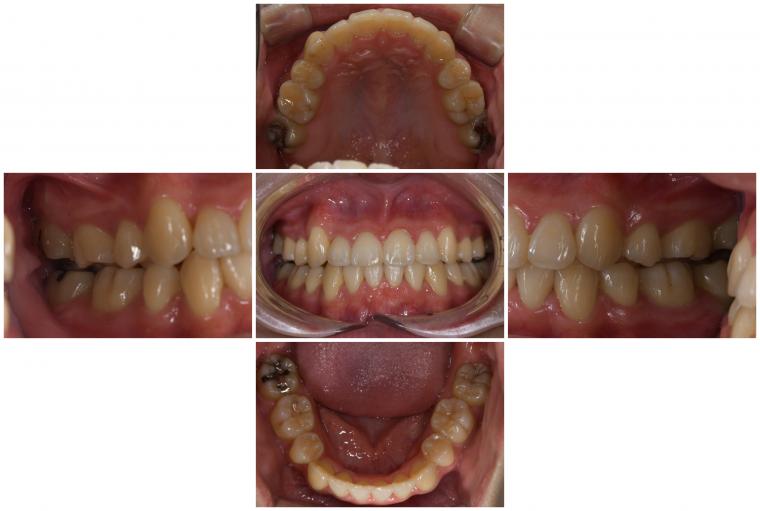

After

【治療内容】 ワイヤー矯正×マウスピース矯正

【症状】 前歯部のガタつき かみ合わせが悪い

【治療期間】 2年

【治療リスク】 左右対称にならない場合がある。

希望通り歯が動かない場合がある。

ブラックトライアングルができる可能性がある。

嘔吐反射が強い場合、マウスピース矯正が できない場合がある。

重度歯周病の方は、歯の揺れがひどくなる場合がある。

歯肉が退縮する場合がある。